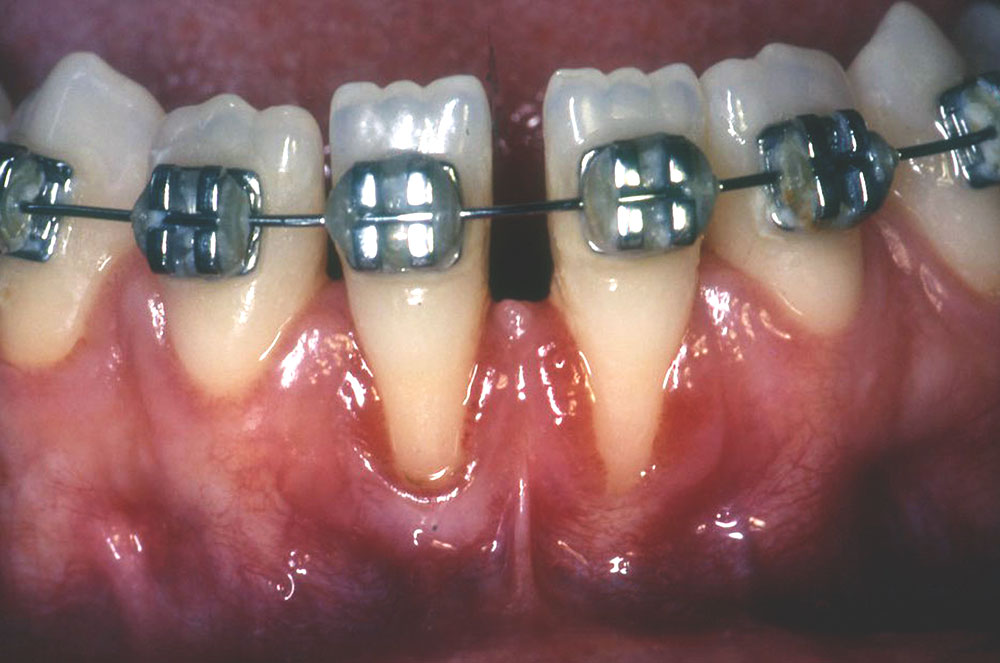

From www.istockphoto.com

Orthodontic Treatment With Gingival Recesion Stock Photo Download Orthodontic Gingival Recession Thin periodontal phenotype is associated with increased risk of recession during orthodontic treatment. further randomized clinical studies including clinical examination of hygiene and gingival condition before, during and after. a thin gingival biotype, presence of previous gr, baseline width of keratinized gingiva and facial gingival. several factors have been suggested to influence the occurrence of gingival recession. Orthodontic Gingival Recession.